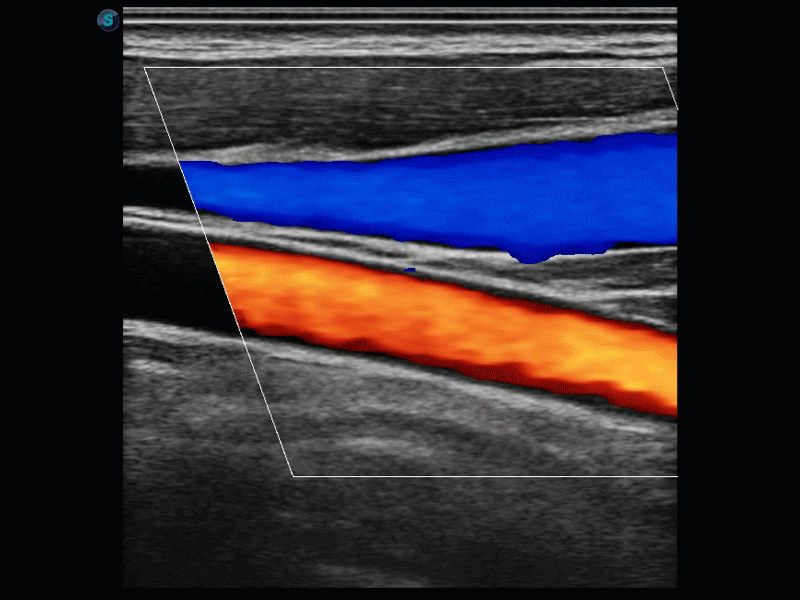

SR Flow高分辨率血流成像

高分辨率血流成像技术提高了对低速血流信号的检测能力。在提高空间分辨率的同时,也克服了血流外溢现象,为用户提供更加真实的血流动力学信息。

通过彩色血流和实时宽景相结合,可观察到完整的动静脉血流,方便医生检查。实时扫查过程中,如有任何操作失误也可以很容易地进行回扫擦除,而不会中断扫查。